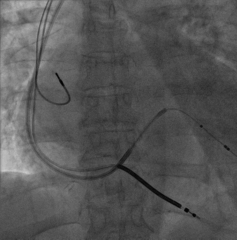

手术经过:首先冠脉造影延迟显影可见冠状窦开口及靶静脉大致走行

AP

LAO45

6225i球囊造影可见轻微夹层,远端未显影

6250VIS鞘管直接造影可见分支显示良好

LAO